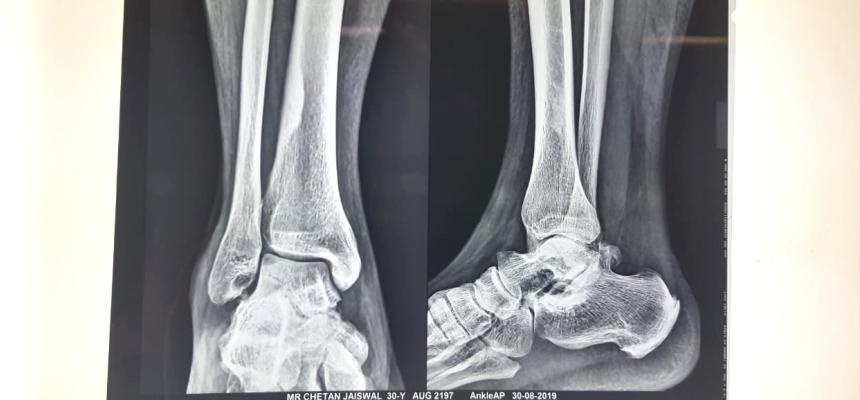

: A team headed by Dr. Girish Bhalerao, Consultant Orthopedic Joint Replacement Surgeon, Wockhardt Hospital, Mira Road, successfully helped a 30-year-old Chetan Jaiswal suffering from a rare condition called Posterior Ankle Impingement Syndrome, to stand on his feet again. The patient encountered ankle pain, difficulty in walking and standing up for a longer time, underwent an arthroscopic decompression with capsular repair keyhole surgery.

Dr. Girish Bhalerao, ConsultantOrthopedic Joint Replacement Surgeon, Wockhardt HospitalMira Road, said, “The patient presented with a history of right Posterior ankle pain leaving him immobile. The probable cause of it was walking on the forefoot. Moreover, the patient neglected it because of the excessive body weight as he weighed 105 kgs. His MRI revealed that there was a swelling of the posterior ankle and he complained of pain with forced flexion. Thus, the patient suffered from a condition called Posterior Ankle Impingement Syndrome (PAIS).”

“The patient underwent arthroscopic decompression with capsularrepair keyholesurgery on 13th December 2019. Arthroscopic Posterior Ankle Decompression with Excision of OS Trigonum – extra (accessory) bone growth that sometimes develops behind the ankle bone (Talus). The surgery lasted for one hour. The patient was discharged after 2 days. The advantages of this surgery are that there is minimal hospital stay, and the patient is given antibiotics and can move freely after the surgery. He was suggesteda physiotherapy program that includes soft tissue therapy, stretching or mobilization of restricted joints. if Mr. Chetan wouldn’t opt for a surgery chances were forAnkle arthritis, severe pain, because of which patient had loss of ankle function.Lifestyle Modification will definitely help in such cases.“suggested Dr Bhalerao.